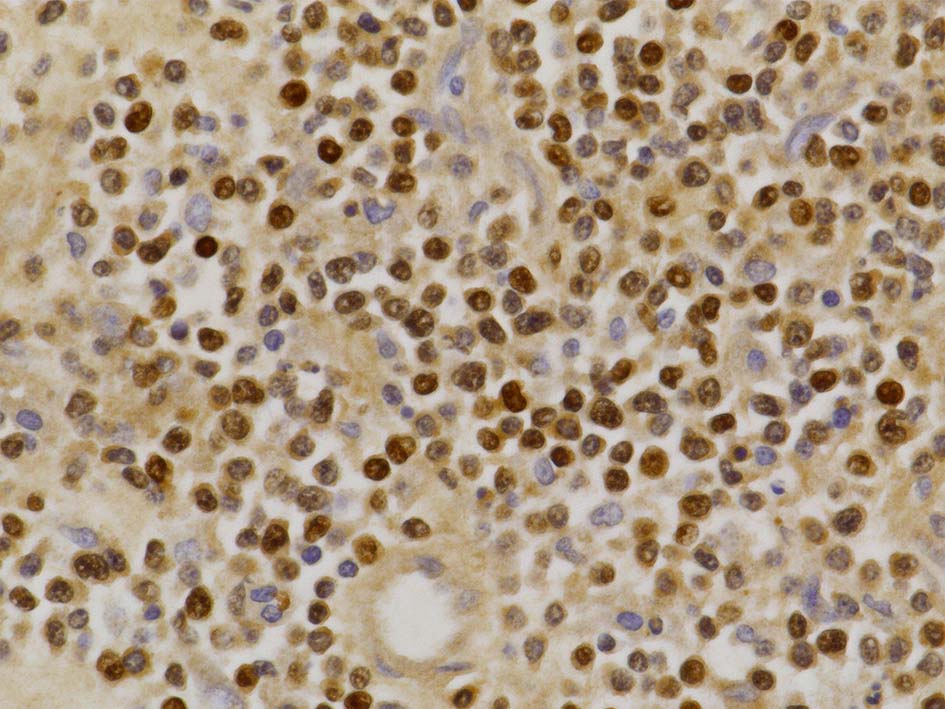

免疫染色

病理診断: Extranodal NK/T-cell lymphoma, nasal type of the testis

LCA(CD45)+, CD20+(focalに陰性), CD79a+, PAX5+, CD5-, CD10+, BCL6+が多い, MUM1-, BCL2+, cyclinD1-, MIB1 LI; very high(>80%). EBER-ISH-.